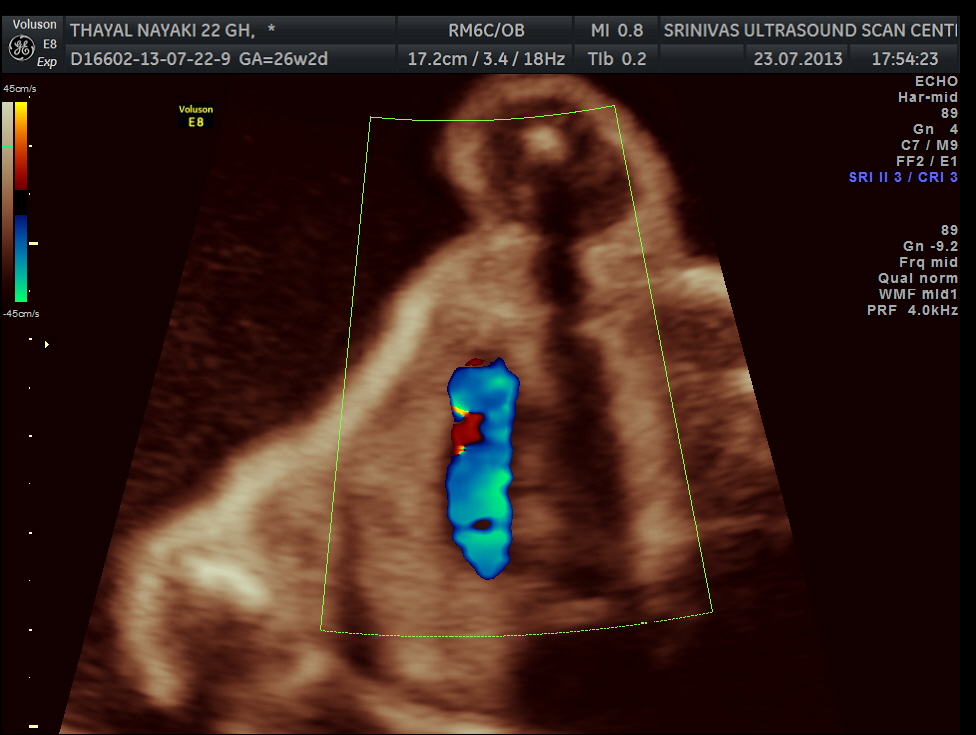

vsd is seen in the picture below.

generally colour flow imaging is not said to be very helpful